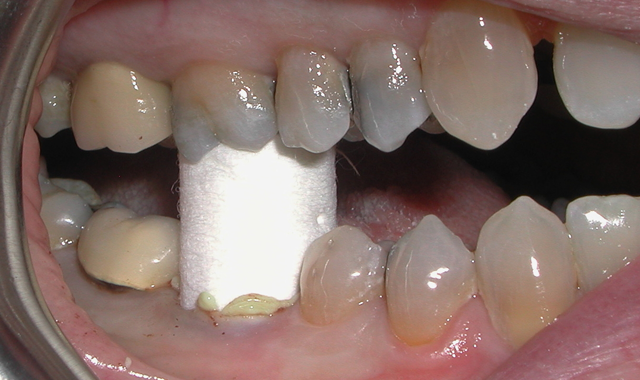

Fig. 1

A 60-year-old male patient presented complaining of pain from the lower right first molar. Upon clinical examination, tooth #30 was sensitive to percussion and had a fractured disto-occlusal-lingual amalgam.

After discussion with the patient and effective local anesthesia, the existing amalgam was removed to reveal caries extending into the pulpal tissue (Fig. 1).